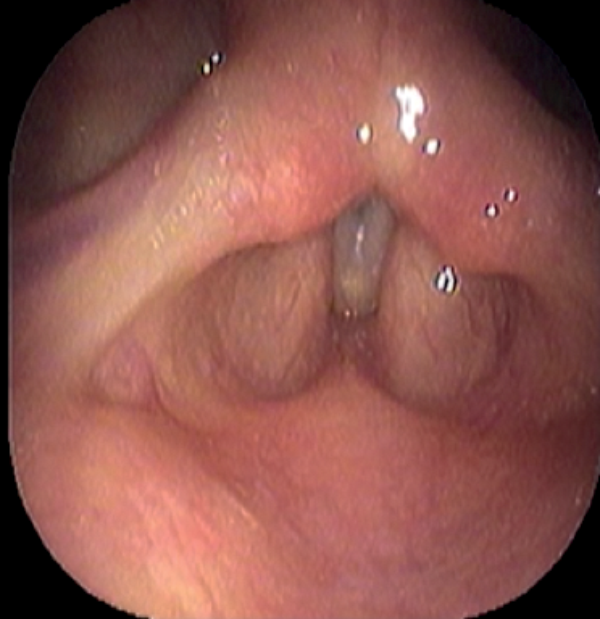

Short-term complications include perforation of the inner perichondrium and asymmetric laryngofissure. In the long-term, implant infection is rare. Hoarse voice or breathy voice can occur as well as recurrence of symptoms in about 10 % of cases. Revision surgery is rare. If it is required, this is usually due to breathy voice from a too wide titanium bridge. The long-term outcomes of this procedure are good. Figure 19 shows the vocal cords before and after surgery.

Figure 19: top 2 pictures) Before adduction, bottom 2 pictures) after adduction.